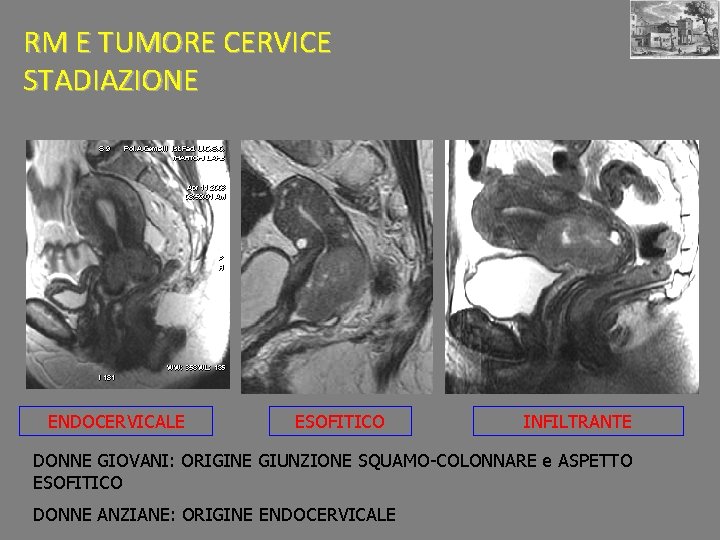

RM E TUMORE CERVICE STADIAZIONE ENDOCERVICALE ESOFITICO INFILTRANTE DONNE GIOVANI: ORIGINE GIUNZIONE SQUAMO-COLONNARE e ASPETTO ESOFITICO DONNE ANZIANE: ORIGINE ENDOCERVICALE